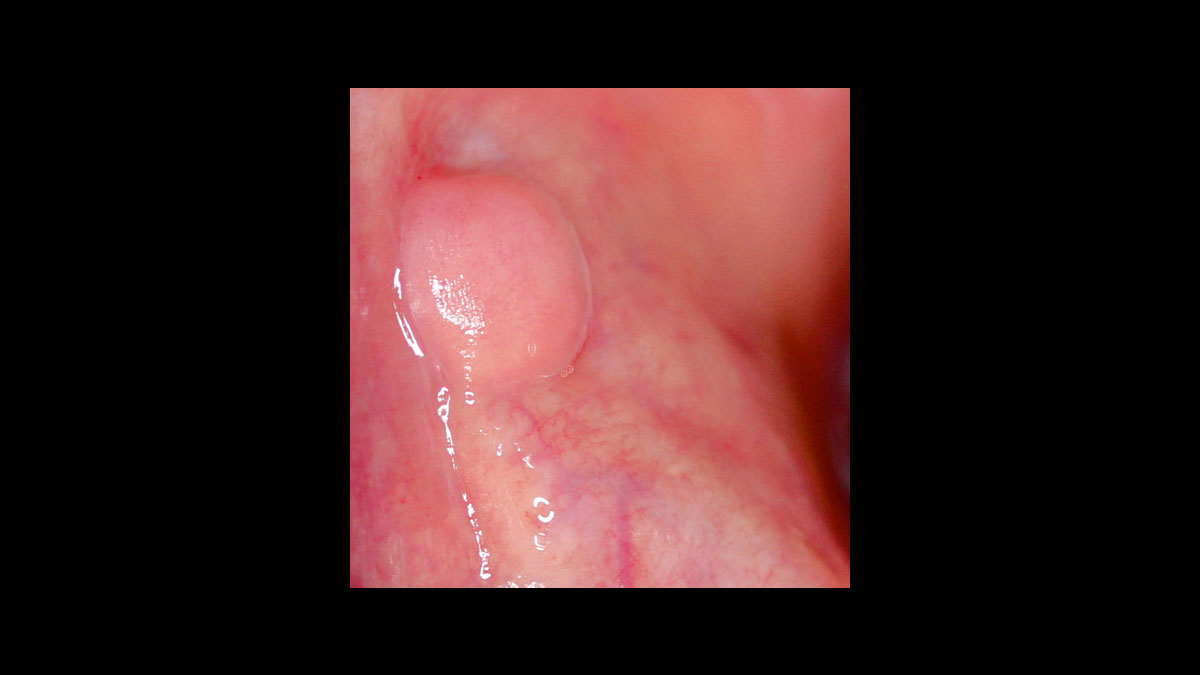

Fibrome